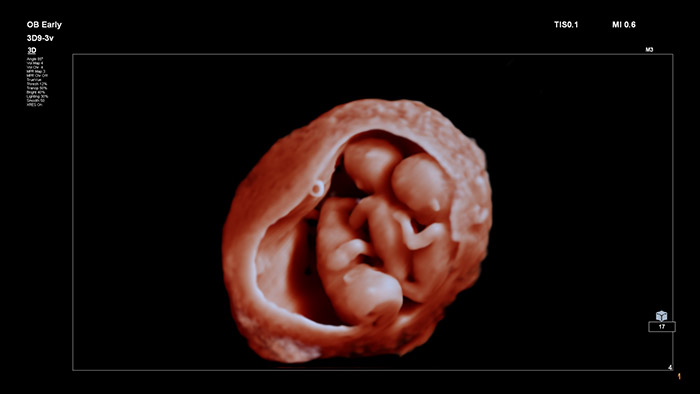

Gracias a sus imágenes innovadoras y con un alto nivel de detalle, así como a la posibilidad de manipular un fotoemisor virtual, TrueVue ofrece imágenes increíblemente realistas del feto durante el embarazo tanto a los profesionales sanitarios como a las futuras madres.